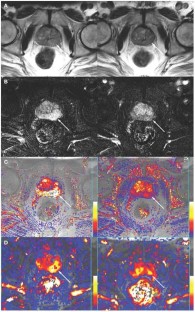

Angiogenesis is an integral part of benign prostatic hyperplasia, is associated with prostatic intraepithelial neoplasia and is a key factor in the growth and metastasis of prostate cancer. This review focuses on ultrasound and dynamic MRI in the evaluation of prostate cancer angiogenesis, and compares these techniques to functional CT and hydrogen magnetic resonance spectroscopic imaging. Image-based evaluation of angiogenesis in the prostate has established clinical roles in lesion detection, tumor staging and the detection of suspected tumor recurrence. One limitation of all these imaging techniques, however, is inadequate lesion characterization, particularly in differentiating prostatitis from cancer in the peripheral zone of the prostate, and in distinguishing between benign prostatic hyperplasia and central-gland tumors. Ultimately, local availability, expertise and the need to minimize patients' radiation burden will influence which technique is used in prostatic evaluations.

Padhani AR et al. (2000) Dynamic contrast enhanced MRI of prostate cancer: correlation with morphology and tumour stage, histological grade and PSA. Clin Radiol 55: 99–109

Engelbrecht MR et al. (2003) Discrimination of prostate cancer from normal peripheral zone and central gland tissue by using dynamic contrast-enhanced MR imaging. Radiology 229: 248–254

Buckley DL et al. (2004) Prostate cancer: evaluation of vascular characteristics with dynamic contrast-enhanced T1-weighted MR imaging—initial experience. Radiology 233: 709–715

Kiessling F et al. (2004) Simple models improve the discrimination of prostate cancers from the peripheral gland by T1-weighted dynamic MRI. Eur Radiol 14: 1793–1801

Ito H et al. (2003) Visualisation of prostate cancer using dynamic contrast-enhanced MRI: comparison with transrectal power Doppler ultrasound. Br J Radiol 76: 617–624